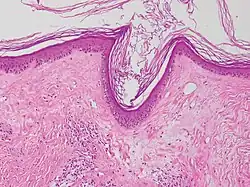

Vacuolar interface dermatitis, with lymphocytes in the dermis and epidermis (black arrow indicates one), and vacuolization (white arrow) at the dermoepidermal junction.

Generally/Not otherwise specified Typical findings, called "":[2]

• Mild inflammatory cell infiltrate along the dermoepidermal junction (black arrow in image)

• Vacuolization within the basal keratinocytes (white arrow in image)

• Often necrotic, predominantly basal, individual keratinocytes, manifesting as colloid or Civatte bodies